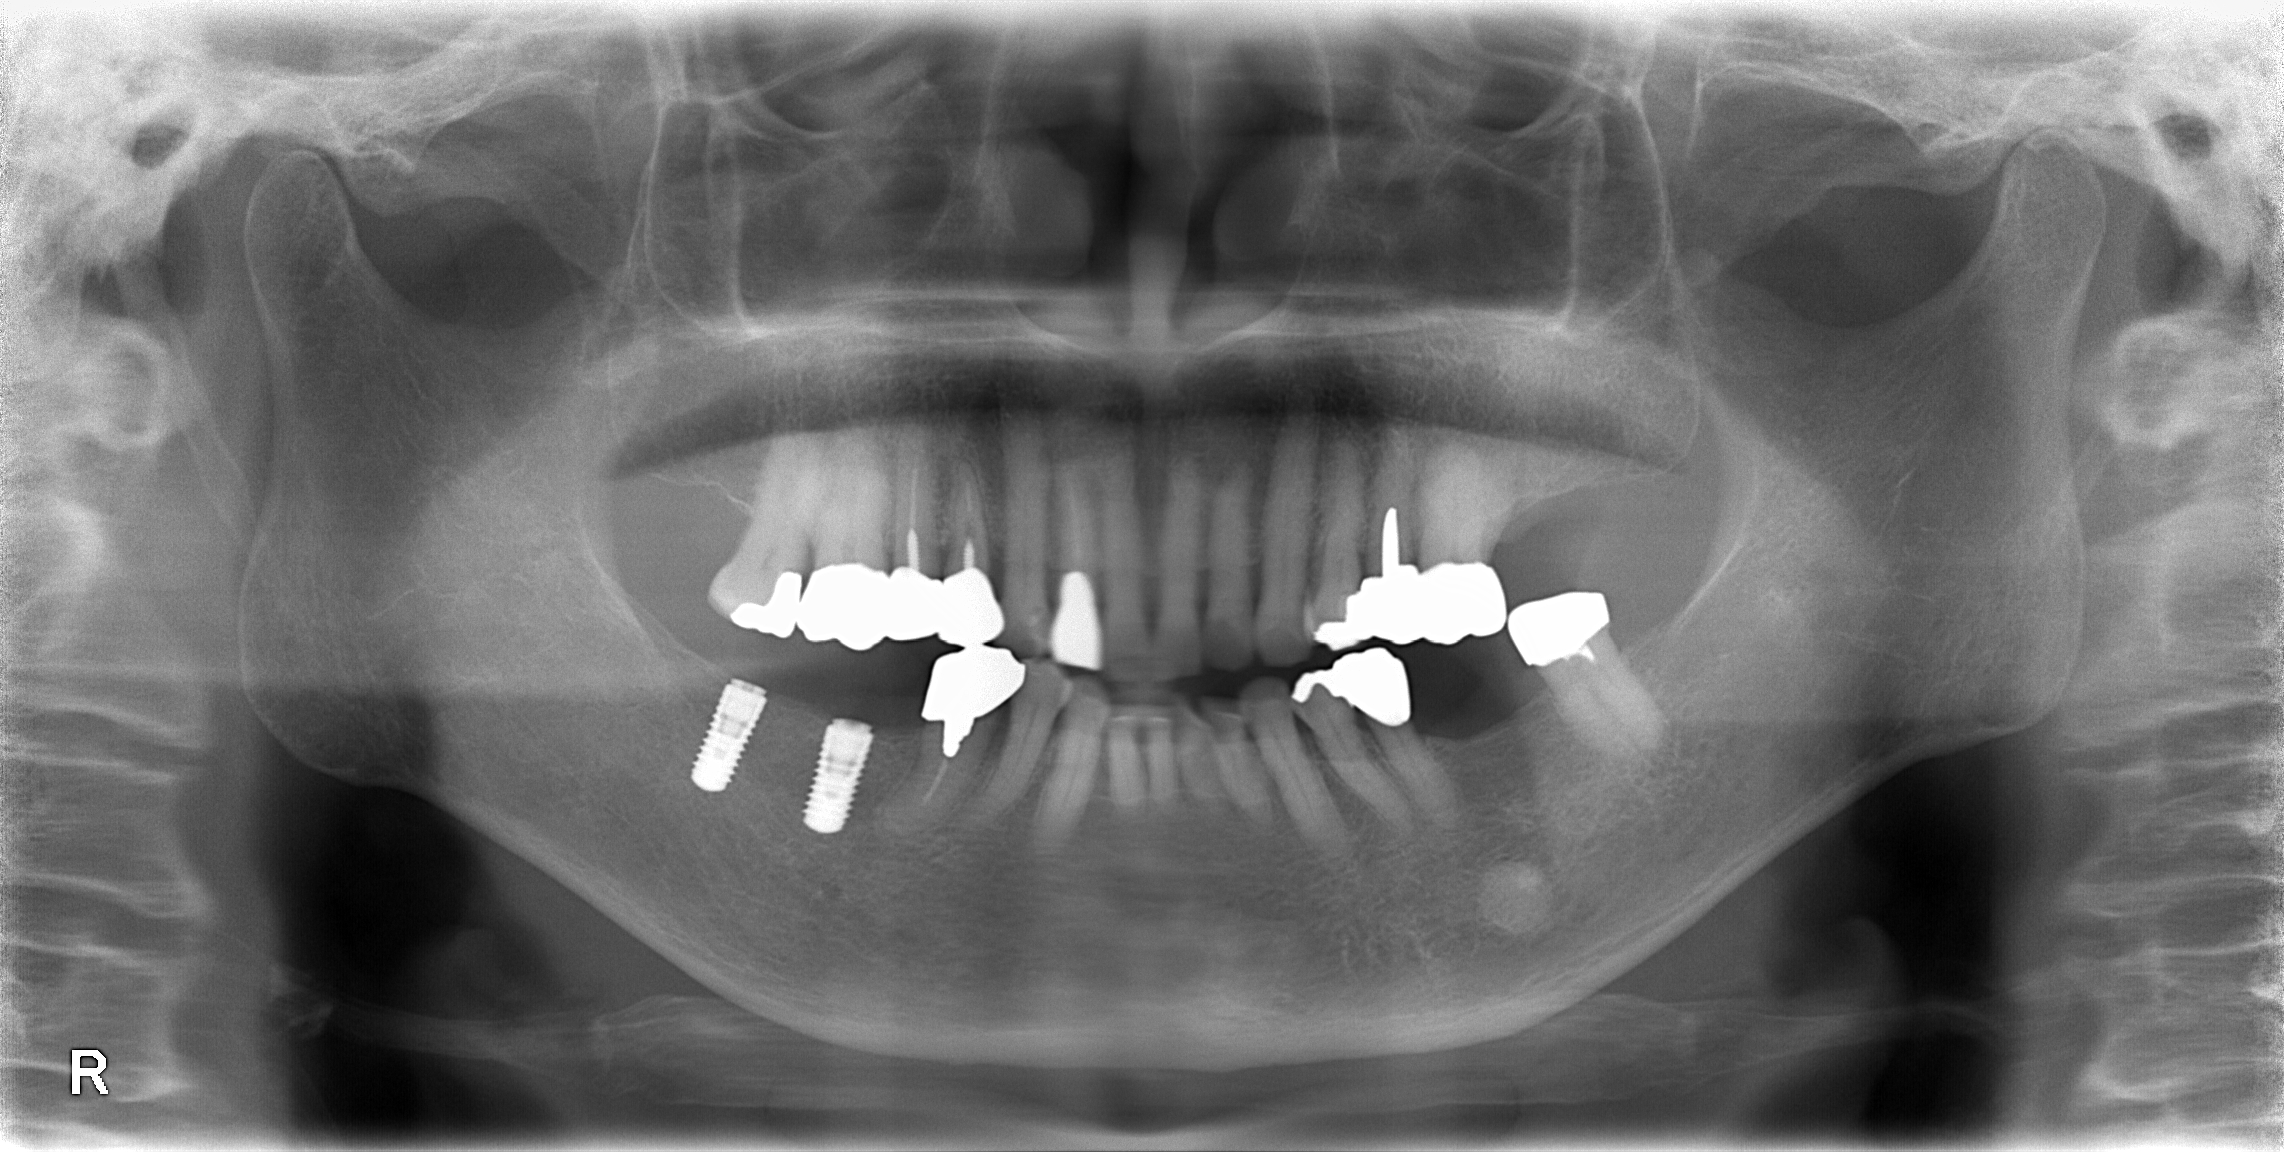

インプラント - 2

重度虫歯からのインプラント・入れ歯治療(*^-^*)